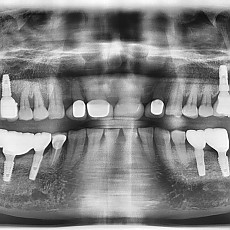

시술전후사진 2 페이지

시술전후사진

Total 62건 2 페이지